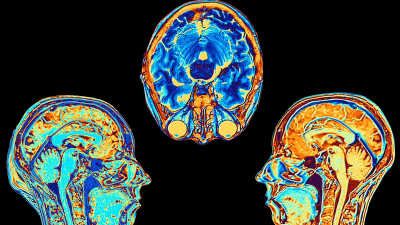

Арахидоновая кислота, важнейший компонент клеточных мембран, содержится преимущественно в липидах — нерастворимых в воде веществах, состоящих из жиров и жирных кислот. Эта кислота жизненно важна для поддержания клеточных функций, здоровья мозга и метаболизма липидов.

Новое исследование Университета Южной Австралии предполагает, что колебания уровня метаболитов — мелких молекул, участвующих в обмене веществ, — лежат в основе развития биполярного расстройства и связанных с ним психических заболеваний.

Более высокие уровни липидов, содержащих арахидоновую кислоту, были связаны с более низким риском развития биполярного расстройства. Напротив, повышенный уровень липидов, содержащих линолевую кислоту, незаменимую жирную кислоту, был связан с более высоким риском. Согласно исследованию, это наблюдение указывает на значимость пути, ответственного за преобразование линолевой кислоты в арахидоновую, в модуляции риска развития биполярного расстройства.

Результаты исследования также подчёркивают ключевую роль арахидоновой кислоты в развитии мозга младенца. Грудное молоко является естественным источником арахидоновой кислоты для младенцев, и её часто добавляют в детские смеси вместе с незаменимыми жирными кислотами, такими как докозагексаеновая кислота. Нарушения в метаболизме арахидоновой кислоты в этот критический период могут способствовать возникновению биполярного расстройства и когнитивных нарушений в более позднем возрасте, говорится в исследовании.